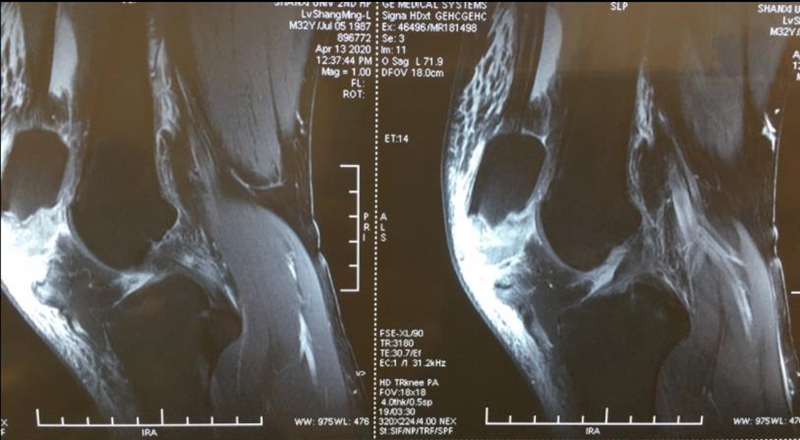

一、入院检查

1.DR正、侧、轴、左右斜位;

2.CT,MR;明确骨折类型,排除半月板、前后交叉韧带、侧副韧带、髌韧带和股四头肌扩张部损伤情况;

吕某,男,32岁,左髌骨下极撕脱骨折7天,2020年4月16行“双套固定法”手术。

术前资料